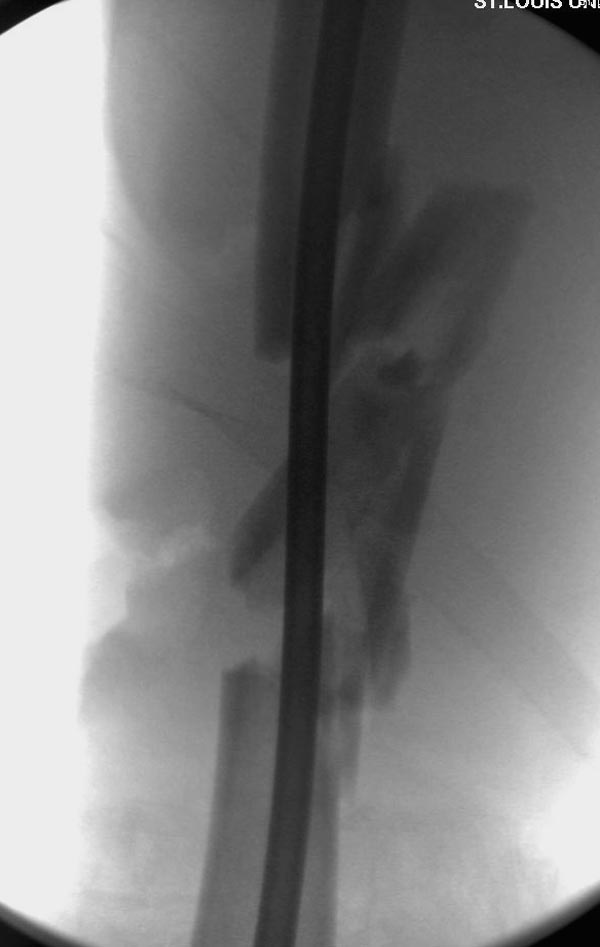

Здесь выставлен ренгенограммы больного, ему 21, травму получил в результате высокоскоростной погони на украденной машине, которая закончилась смертью трех остальных “боевых комрадов”. Начатую коллегой открытую операцию на шейке пришлось закончить мне, установкой винтов и ретроградной фиксацией бедра. Выписка в обычное сроки и наблюдался амбулаторно. Каждый раз напоминали о возможности осложнений ввиде несращения! По истечению 4 месяцев появились признаки варусной деформации. На СТ срезах несращение шейки и бедра. Риминг, замена на более толстый гвоздь и вальгусная остеотомия.

Сразу скажу, что пациент вчера (8.04) прооперирован - артротомия, остеосинтез мыщелков большеберцовой кости канюлированными винтами, открытая репозиция отломков бедренной кости, ретроградный БИОС, остеосинтез надколенника (центральных его отломков) спицами с проволочной петлей. Двухкратная попытка закрытой репозиции шейки на операционном столе после синтеза бедра - абсолютно неэффективна. Учитывая продолжительность и травматичность операции, шейка отложена на 2-й этап. Плечо наверное на 3-й (если вообще делать). Снимки постараюсь предоставить, но чуть позже.